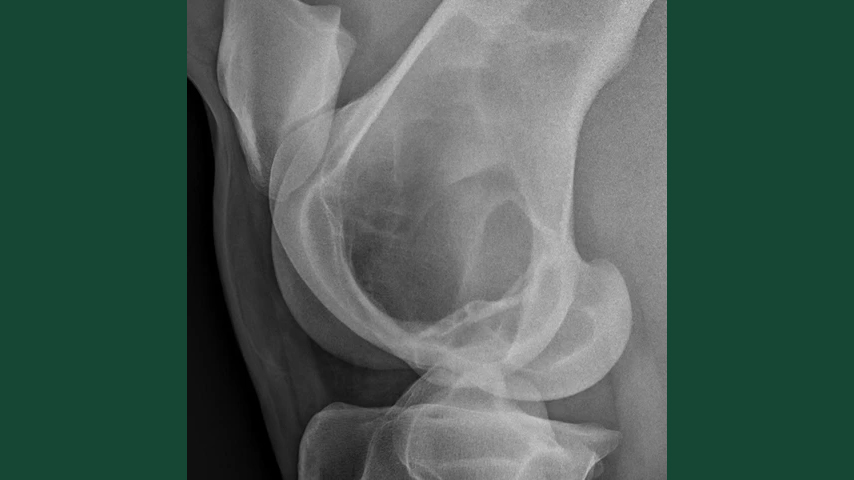

Röntgenbild tagen från sidan av knäleden hos häst.

I en fallrapport från Universitetsdjursjukhuset vid Sveriges lantbruksuniversitet beskrivs en ovanlig cysta hos en 10-årig varmblods valack. Hästen var lindrigt halt på vänster bakben och röntgenbilder visade ett väldefinierat område av minskad röntgentäthet i nedre delen av det vänstra lårbenet nära knäleden. Förändringen definierades som en mycket stor bencysta med ovanligt utseende.